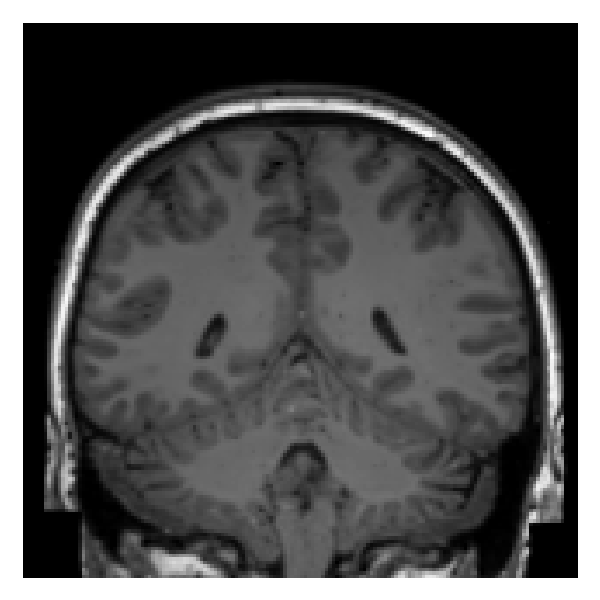

Magnetic Resonance Imaging (MRI) of the head preserves cranial and facial structures that can identify individuals [35, 28]. To improve privacy, researchers often remove or replace information that could identify a person. Defacing, completely or partially, removes facial features, retaining structures, such as the skull and skin [6, 43, 14], whereas skull-stripping isolates only the brain parenchyma, providing stronger privacy protection [9]. However, recent studies have shown that, even after skull stripping, brain parenchyma retains participant-specific anatomical patterns that can link MRIs from the same individual, see Figure 1. Using supervised learning, Valizadeh et al. and Jäncke et al. demonstrated participant matching from longitudinal T1-weighted scans [45, 19]. Wachinger et al. proposed BrainPrint for characterizing individual brain morphology and applied the framework for subject identification based on supervised learning [47], which Puglisi et al. extended to DeepBrainPrint, a deep learning framework [36]. Chauvin et al. proposed a keypoint-based similarity based method to match T1w MRI scans from the same participants and demonstrated that scans from close relatives are more similar to each other than scans from unrelated persons [7].